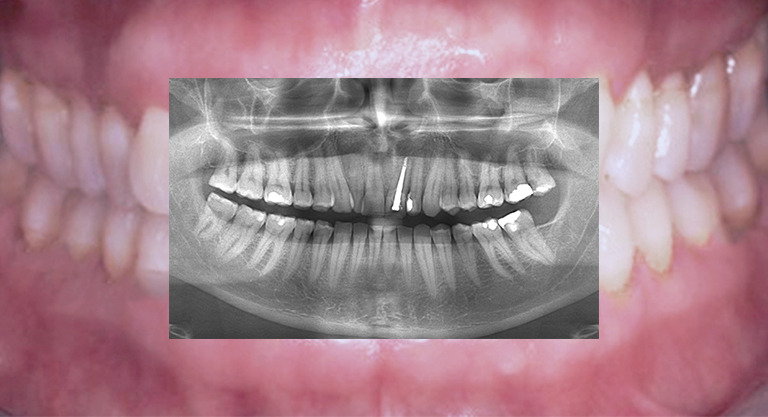

Diagnostik mittels 2-dimensionaler Bildgebung

3-dimensionale Volumentomographie DVT/OPT